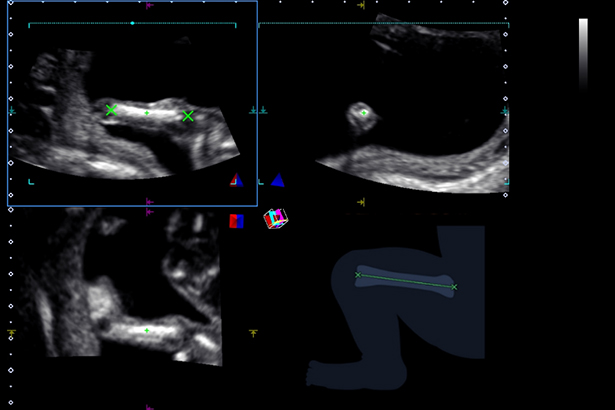

根據胎兒的容積數(shù)據,可以半自動地測量大腿或者上臂的部分體積,然后根據測量結果推斷出估計體重 EFW。

在水平方向和垂直方向掃描,并從連續(xù)采集的動態(tài)圖像數(shù)據中重建三維圖像。通過設置擺動操作的角度或滑動操作的距離,可以輕松地重建容積圖像。